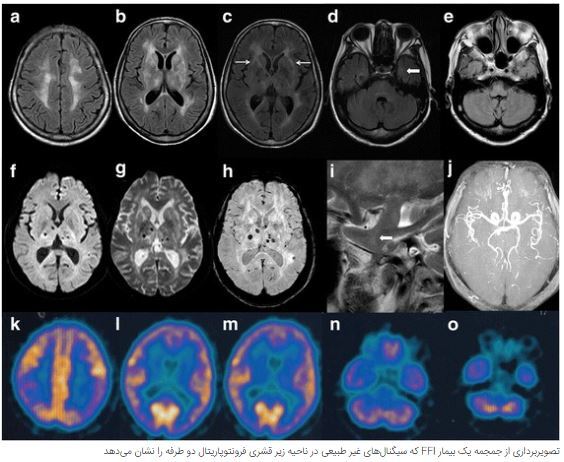

تصور کنید یک بیماری ژنتیکی نه‌تنها خواب شما را از بین ببرد بلکه جانتان را نیز بگیرد. این دقیقاً همان چیزی است که بیماری بی‌خوابی کُشنده خانوادگی (FFI) انجام می‌دهد.

این بیماری نادر مغز و سیستم عصبی مرکزی را درگیر می‌کند و باعث بی‌خوابی مداوم، از دست دادن حافظه، و تشدید انقباضات عضلانی می‌شود. FFI یک بیماری پیش‌رونده است و هیچ درمانی برای آن وجود ندارد.

در سراسر جهان تنها بین ۵۰ تا ۷۰ خانواده به این بیماری مبتلا هستند.